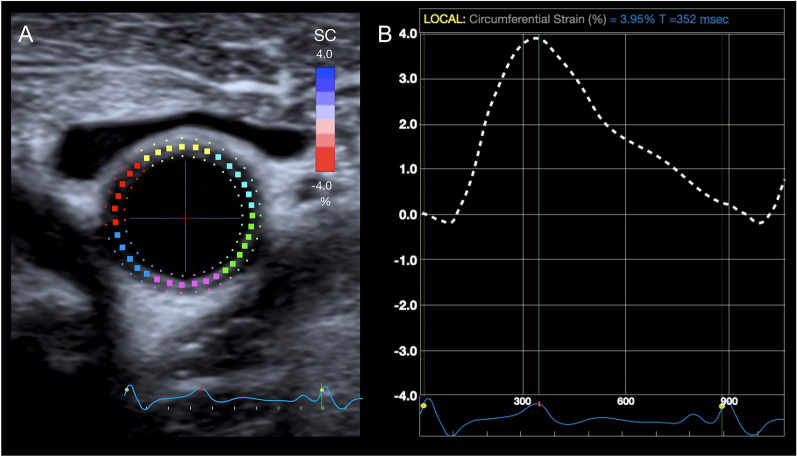

Abstract Image